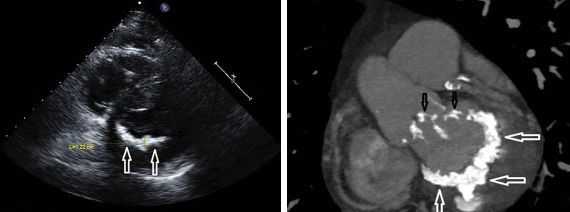

Пролапс митрального клапана диагностируется у всех больных с синдромом Марфана, реже встречается пролапс трикуспидального клапана. Дилатация корня аорты наблюдается у всех новорожденных и имеет тенденцию к прогрессированию. Изменение аортального клапана с регургитацией крови наблюдается существенно реже. Нередко имеется сочетанное поражение митрального и трикуспидального клапанов. Характерная патологическая особенность при этом синдроме — миксоматозное утолщение митрального и трикуспидального клапанов, укорочение их хорд, а также дилатация корня аорты и легочной артерии. Гистологически определяются сильно разорванные эластические и коллагеновые волокна, они беспорядочно расположены и фрагментированы с увеличением интерстициальной субстанции.

Неонатальный синдром Марфана представляет собой сочетание арахнодактилии, внешних дисгармонических черт развития, пролапса обоих атриовентрикулярных клапанов и дилатации обоих аортальных и легочных корней. Морфологически находят миксоматозные наложения на клапанах, аневризму синуса Вальсальвы, миксоматозную ткань вокруг атриовентрикулярного узла.

К наиболее характерным нарушениям со стороны ССЗ относятся ПМК и дилатация синусов Valsalva. Клинические проявления этих нарушений в виде митральной peгургитации, аортальной регургитации и расслоения аорты и, при отсутствии лечения, становятся причиной большинства случаев ранней смерти, в результате средний возраст таких пациентов < 40-50 лет. У детей наблюдается тенденция к более тяжелым поражениям митрального клапана, тогда как поражения аорты прогрессируют и наиболее вероятны в подростковом и более старшем возрастах.

Синусы Valsalva часто расширены уже при рождении, а прогрессирование этого нарушения широко варьирует у пациентов в целом и среди их родственников. Таким образом, прогнозирование отдаленного риска развития аортальной регургитации положительно ассоциируется с диаметром корня аорты, а риск развития расслоения аорты менее связан с ее диаметром. Для определения и мониторирования изменений диаметра аорты достаточно трансторакальной ЭхоКГ (ТТЭхоКГ), поскольку при отсутствии расслоения дилатация ограничена проксимальным отделом восходящей аорты, а скорость развития (появления) изменений (в мм/год) невелика.